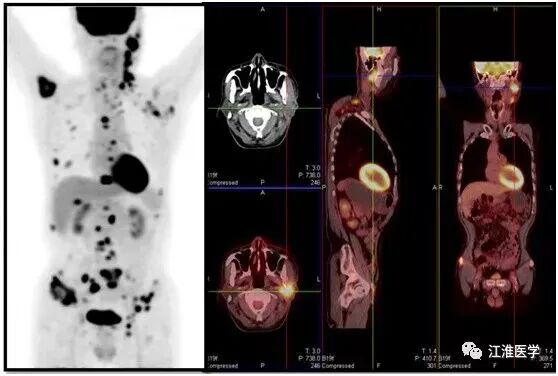

口腔科的医生推荐去找肿瘤科,我查了病人,给他儿子说,老人10年前已经有恶性表现,现在颈部、腋窝已经摸到了很多淋巴结,估计已经转移,患者全身酸痛可能骨头已经有了转移。

“如果条件允许,先做一个全身PET/CT,了解肿瘤的转移情况,再决定下一步的治疗方案”。"赶快帮我们开检查”,“求求你了,能给我们加到明天吗?”,知道了老张的情况后,我已经可以预测他的图像了,“加吧,最多再加加班”,大家也都默默无语。

老张的结果,可想而知,下面的图诉说着血淋淋的故事:

图中左侧的黑白图除了大脑,心脏和膀胱外其余的黑点全是肿瘤病灶,右边的十字指示的是腮腺的复发的恶性肿瘤